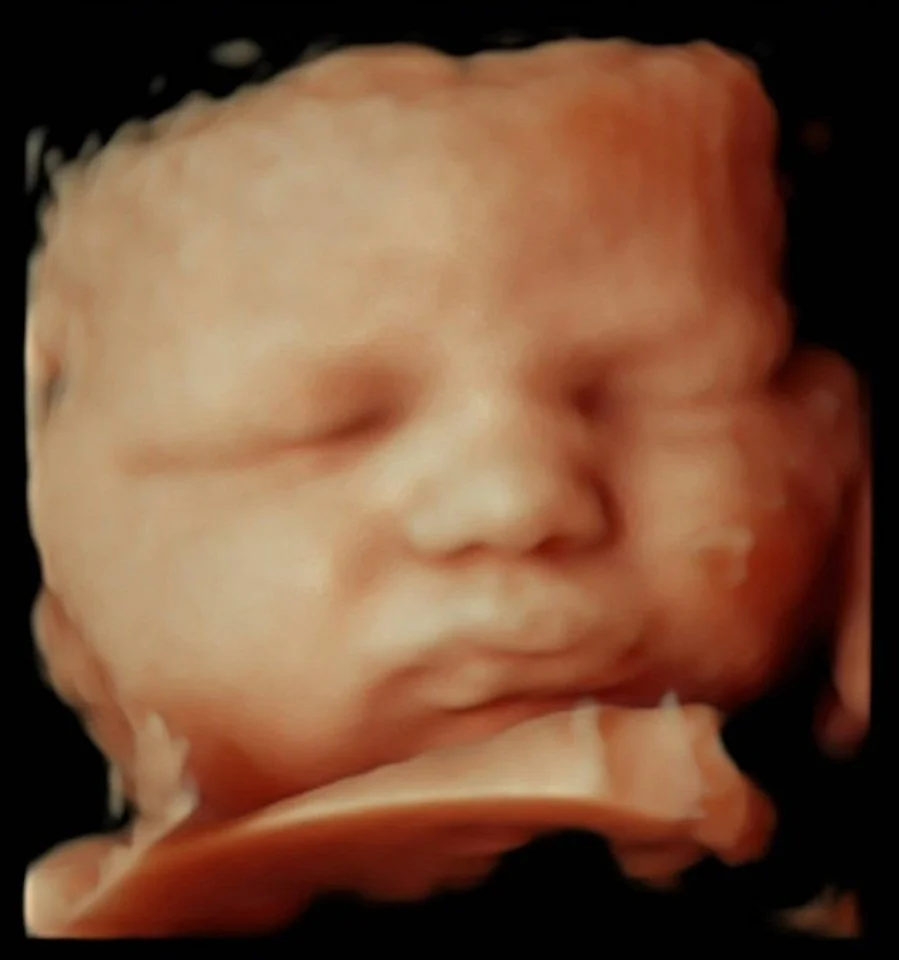

Galerie d'échographies